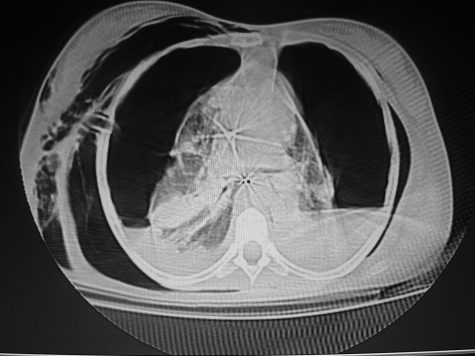

El amplio espectro clínico de la neumonía adquirida en comunidad genera problemas para su diagnóstico. La neumonía producida por Staphylococcus aureus es conocida como necrotizante, de rápida evolución y alta mortalidad. Se describe el caso de una mujer de 14 años con neumonía necrotizante por S. aureus resistente, evolucionó rápidamente a insuficiencia respiratoria requirió ventilación mecánica presento bacteriemia, empiema, neumatoceles, neumotórax bilateral persistente con fistulas broncopleurales que requirieron corrección quirúrgica. No se detectaron factores de riesgo. Los cultivos en sangre, líquido pleural, lavado traqueal fueron positivos y el tratamiento fue exitoso.